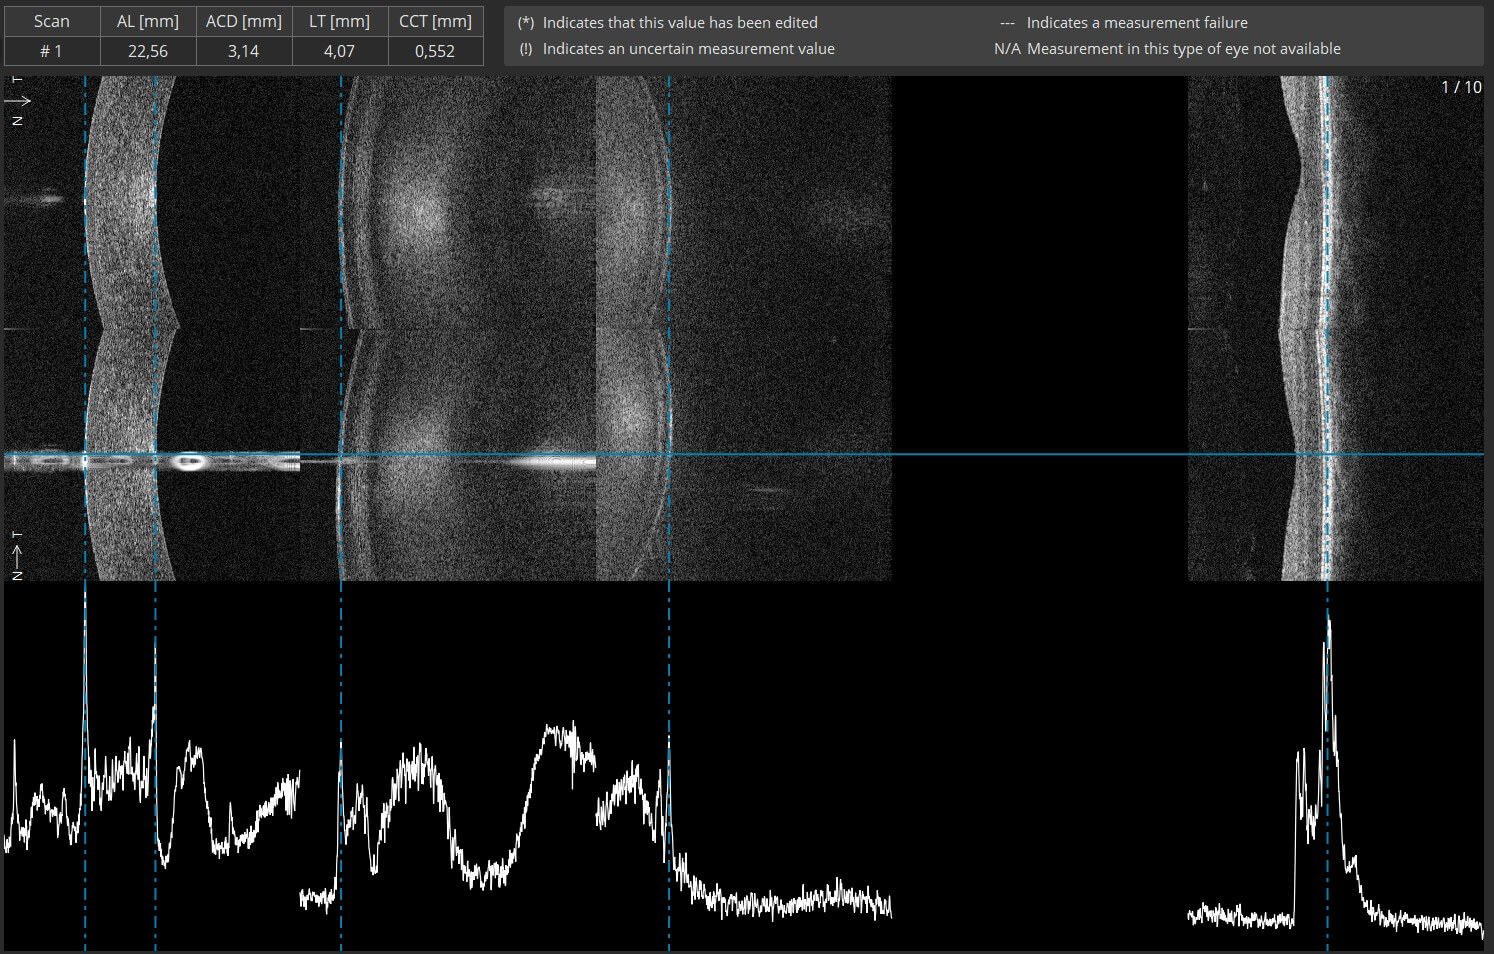

With a unique combination of super-fast scanning at 130,000 scans per second and ultra-high 3μm resolution, this powerful device takes precision, accuracy, and detection of even the finest lesions to a whole new level. The REVO HR is an all-in-one device you can use in a number of ways such as a full colour fundus camera or as a combo, providing simultaneous OCT and fundus images for high quality OCT imaging, including OCT-A.

REVO FC 130

The REVO FC 130 combines the world’s fastest SD-OCT with a non-mydriatic colour fundus camera. Blaze through exams with a scan speed of 130,000 A-scans per second. Featuring our all-new AccuTrack™ real-time hardware-based eye tracker. Operating it is as simple as the push of a button.